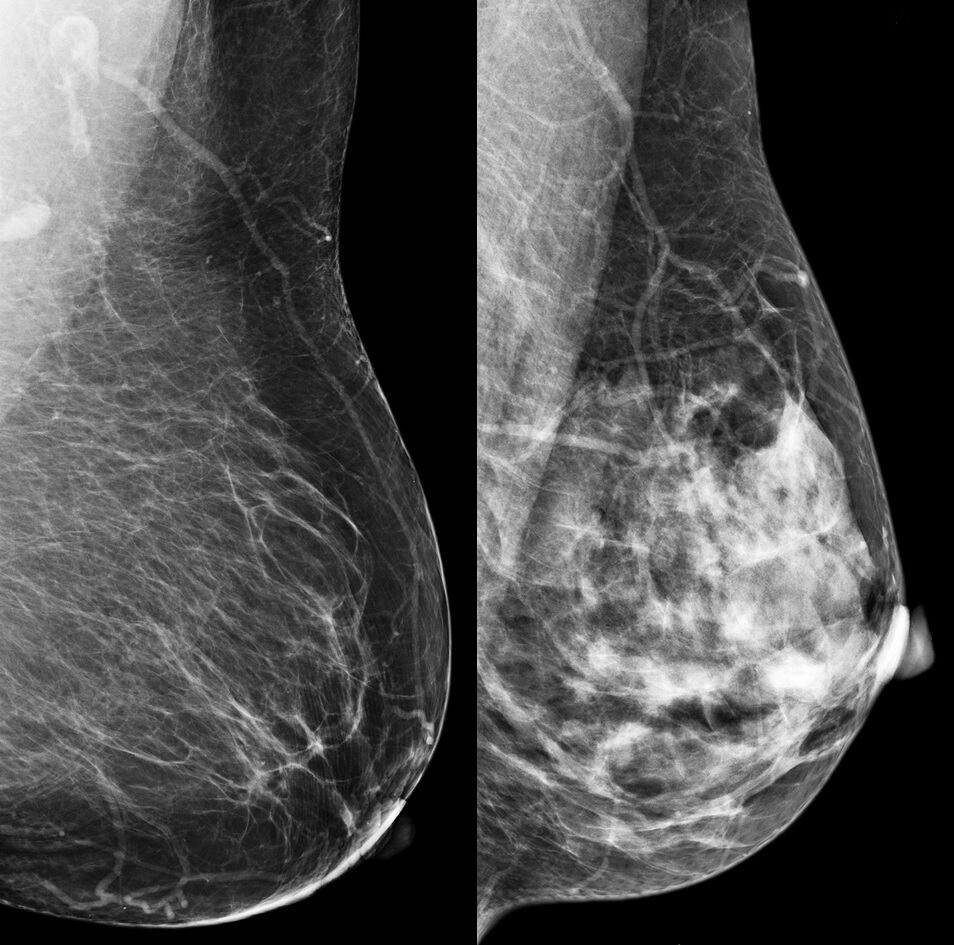

Cada año en el mundo alrededor de 2,2 millones de mujeres son diagnosticadas con cáncer de mama. Las historias dolorosas y de superación, además del llamado de entidades y sobrevivientes para diagnosticarlo a tiempo, hacen que el nombre de la enfermedad sea más conocido.

El cáncer de mama es un tipo de cáncer que se forma en las células de las mamas y su síntomas son: las protuberancias en el pecho, las secreciones de sangre del pezón y los cambios en la forma o la textura del pezón o el seno.